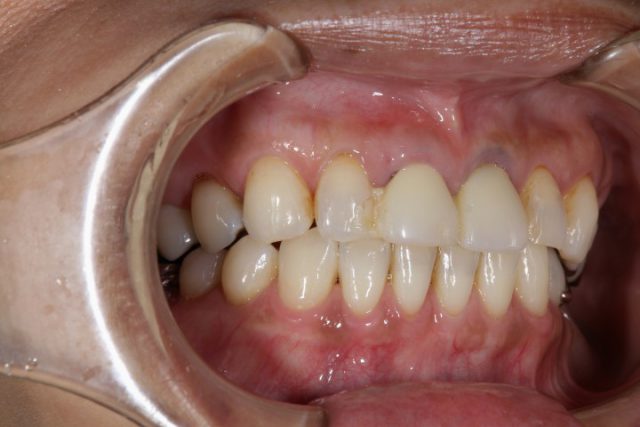

施術後

今回のように以前に施術した詰め物が変色したり、場合によっては欠損してしまったりの時に思い切ってオールセラミックによる施術を検討されてはいかがでしょうか。

歯のストレスというのは小さなことに思えますが、患者様のほとんどが施術後に大きなストレスだったと気づかれます。是非一度口の中にストレスがないかどうかセルフチェックしてみてくださいね!